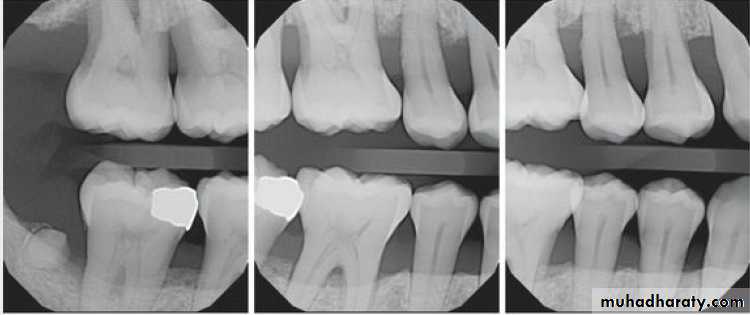

Pattern of bone loss:

Several investigators have analyzed the distance from the CEJ tothe alveolar crest.

The height of interdental bone may be reduced, with the crest perpendicular to the long axis of the adjacent teeth (horizontal bone loss), or

angular or arcuate defects (angular, or vertical, bone loss)

could form.

Parodontitis:

Parodontitis superficialis (mild –to- moderate periodontitis.

Parodontitis profunda (advanced periodontitis)

Parodontitis inter-radicularis (periodontitis in the furcation area).